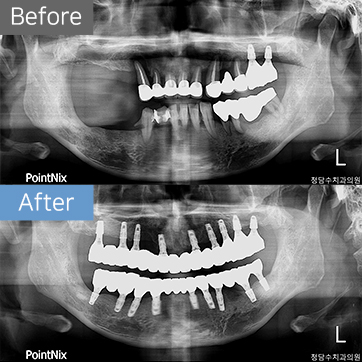

임플란트 50대남 임플란트

50대남 임플란트